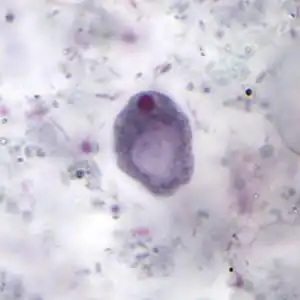

The cysts are 8–10 micrometres in diameter, with a thick wall and a large glycogen vacuole that stains darkly with iodine. Usually harmless, it may cause amebiasis in immunologically compromised individuals. [5][6] As the second form of I. butschlii, cysts have an oval shaped- single nucleus with a prominent nuclear endosome. This form is also large, single, glycogen-filled vacuole called iodinophilous vacuole (glycogen stains with iodine). Cysts are the infective stage of I. buetschlii. Unlike trophozoites, cysts are often found in formed stools.[4]